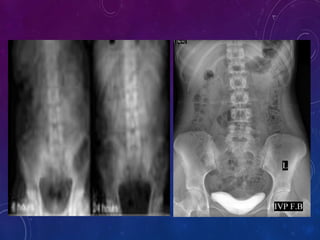

Delayed films in IVU are taken 1-24 hours after injection. Patients should

always be instructed to void prior to delayed films so that a calculus in the

distal ureter seen in the well.

Usual sequence of delayed films is after 1 hr, 3hrs, 6hrs, 12hrs and 24hrs.

Delayed films are used in :

 Cases of obstruction where early nephrogram is seen but collecting

system is not seen

 Long standing hydronephrosis in which renal parenchyma is seen but

collecting system is not visualized until many hours later

 Congenital lesions like non-visualized upper calyceal system with

obstructed ureter

Delayed films: